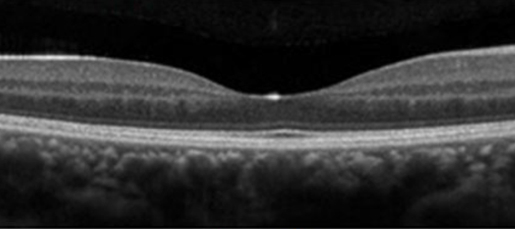

視力低下や見え方に異常を感じない場合は経過観察をします。

視力が低下した場合は、主に黄斑浮腫が生じていることが多いです。黄斑浮腫を改善する治療をします。